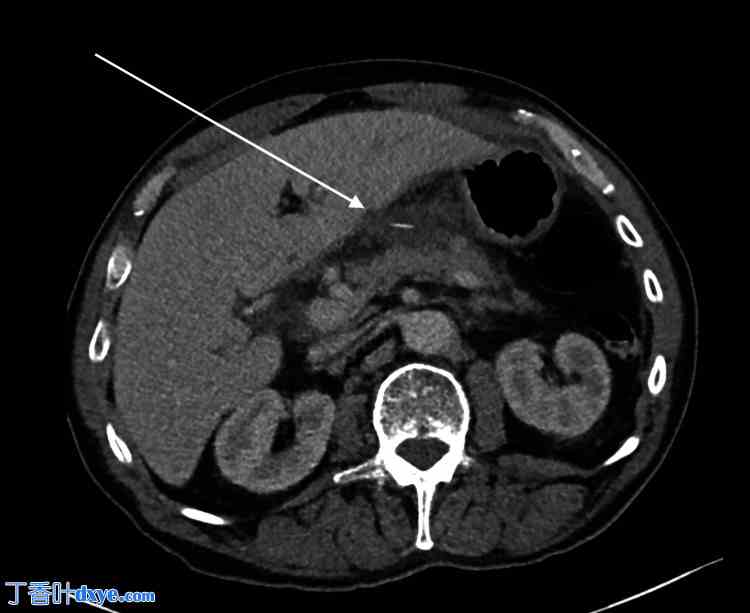

图1. 上腹部CT轴位图像。

箭头指向小网膜囊内的低密度积液和肝包膜下积液,大小为25 × 38 × 33 mm(前后径 × 垂直径 × 头尾径)。该积液中心可见一根线状鱼骨。

AP,前后位;TV,横断面;CC,头尾位